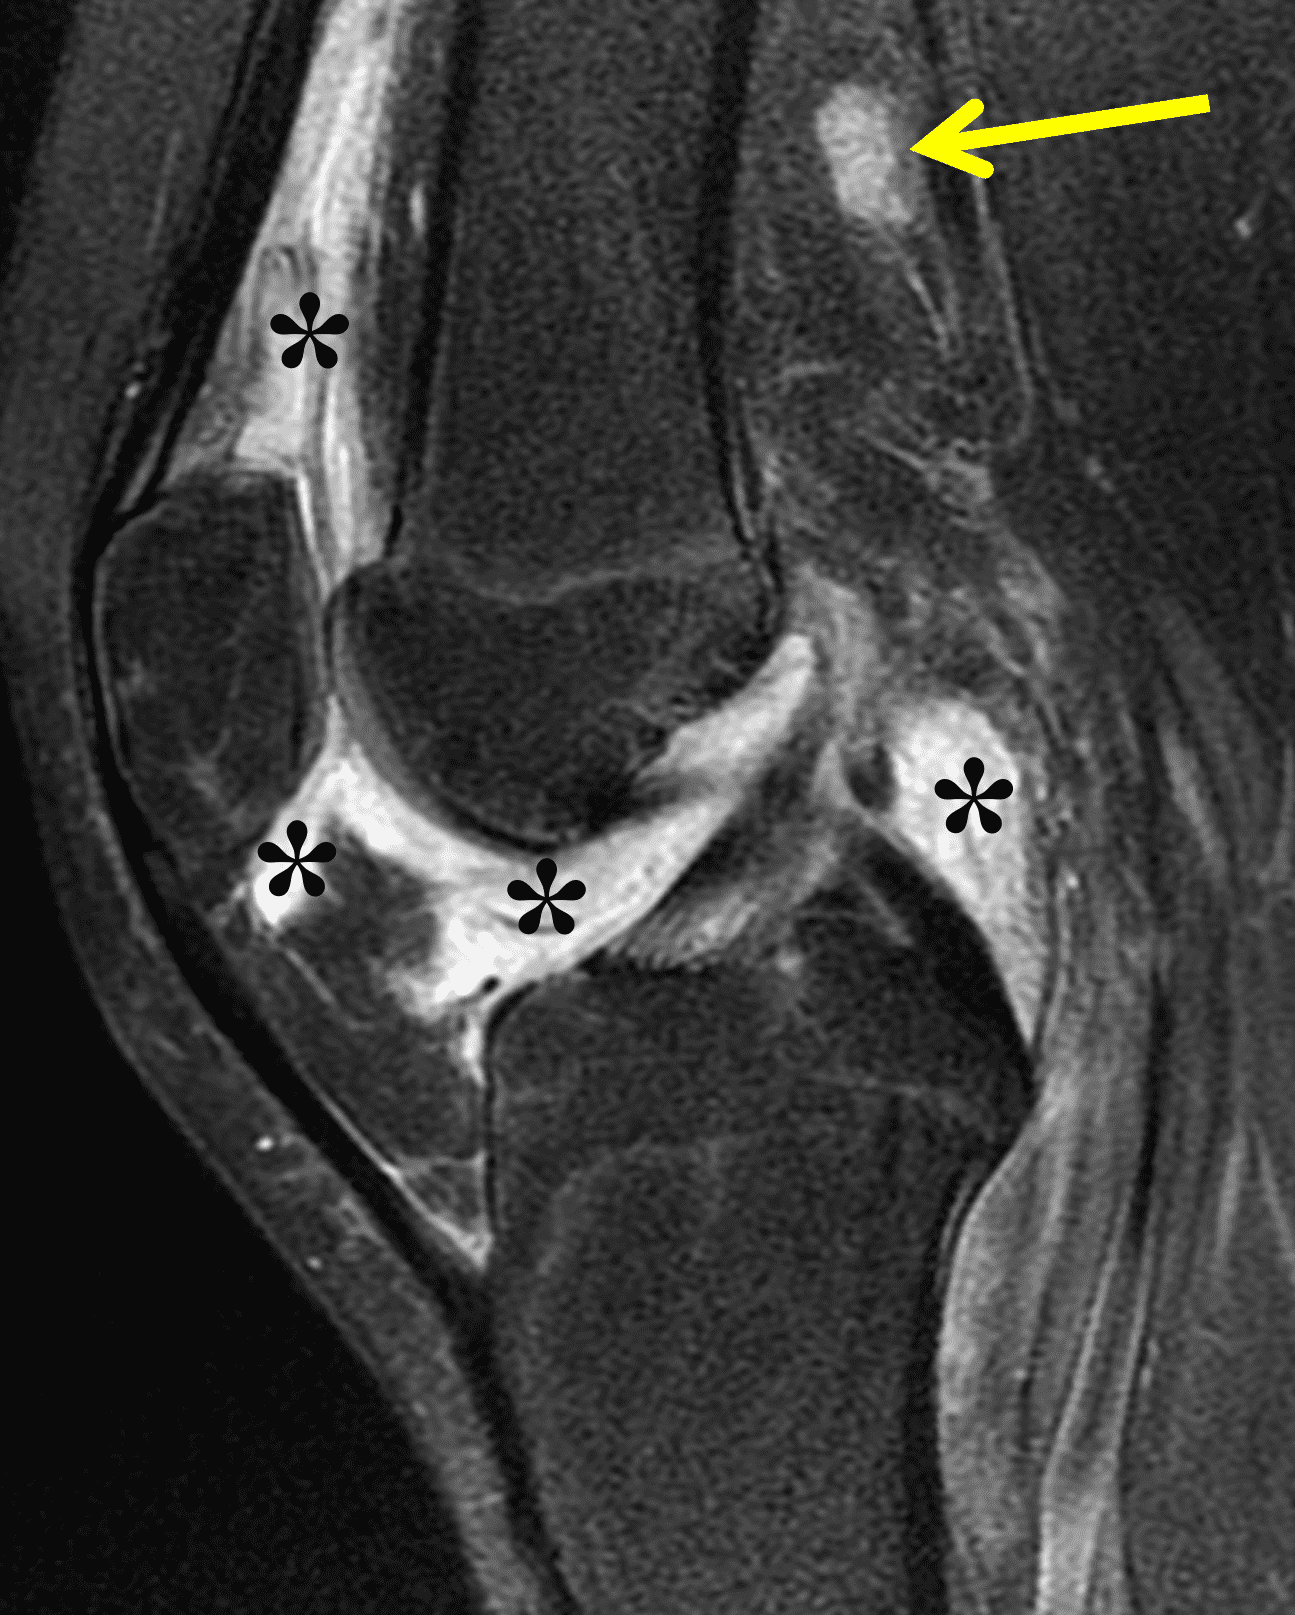

Figure 2: (2A) The coronal image shows a large effusion and severe hypertrophic synovitis (asterisks) in the knee. (2B) On the sagittal image the hypertrophic synovium (asterisks) involves the suprapatellar and infrapatellar recesses as well as the anterior and posterior intercondylar notch. A reactive lymph node (arrow) is present in the popliteal fossa. (2C) The axial image demonstrates myositis (arrows) involving the popliteus and peroneus longus muscles. Note the preserved articular cartilage, lack of erosions, and the absence of subcutaneous or marrow edema.

The causative spirochete invades the synovium, triggering a host inflammatory response that leads to synovial hypertrophy and inflammation, resulting in the characteristic clinical symptoms and imaging findings associated with Lyme arthritis.2 Common MR findings associated with Lyme arthritis include synovitis, joint effusion, popliteal lymphadenopathy, and myositis predominantly involving the popliteus (Figure 4).2,3,9 In contrast to acute septic arthritis due to more common bacteria, subcutaneous edema, marrow edema, erosions, and osteomyelitis are uncommon (Figure 4C).

Figure 4: Lyme arthritis. Fat-suppressed, fluid-sensitive images. (4A) Transverse image shows severe proliferative synovitis in the anterior and posterior joint recesses (arrows). Note the lack of surrounding subcutaneous edema. (4B) In addition to synovitis, the sagittal image shows multiple reactive lymph nodes (red arrows) and popliteal myositis (white arrow). (4C) Coronal image also shows patchy non-joint centered marrow edema in the distal femur and proximal tibia (asterisks), which is uncommon in Lyme disease compared to acute septic arthritis.